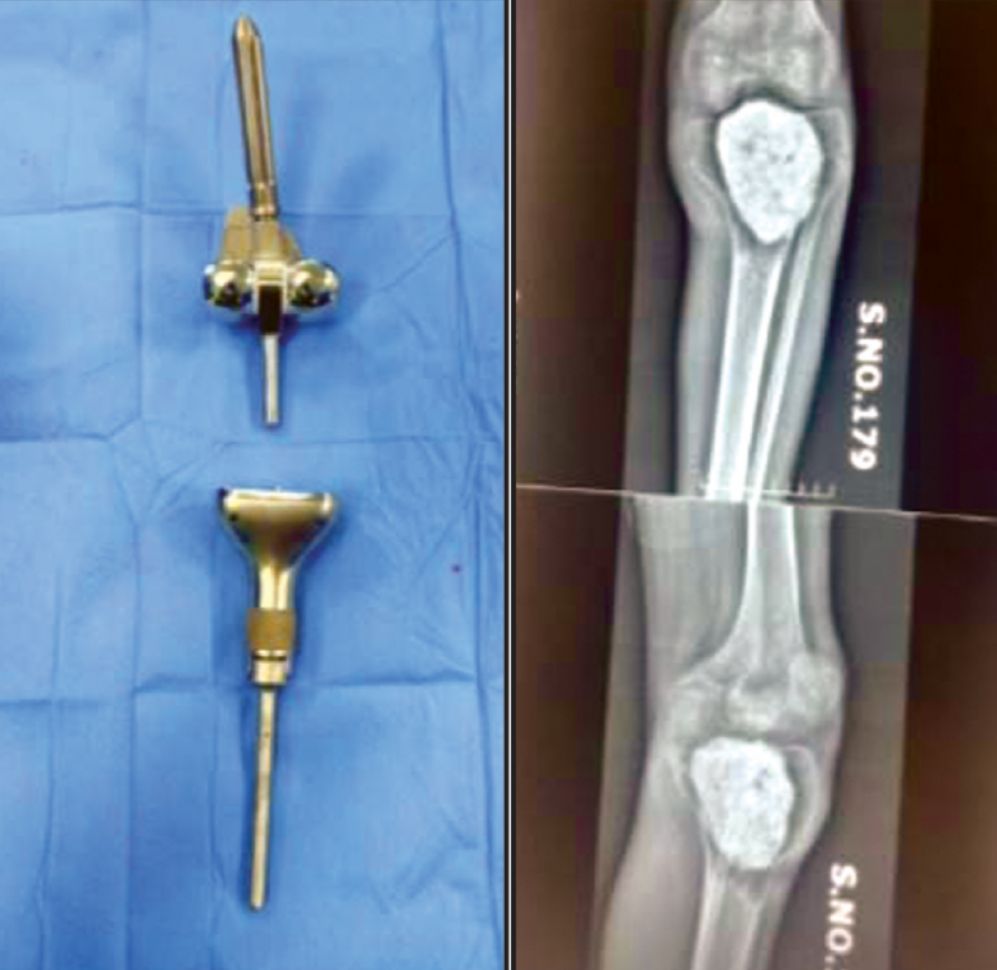

KARACHI: Doctors at Jinnah Hospital have successfully carried out the hospital’s first-ever knee cancer operation, giving a 26-year-old patient a new lease of life with the implantation of an artificial knee, ARY News reported.

According to Dr Farukh, the young patient was suffering from cancer in his knee and lower leg. A four-hour-long surgery was conducted by a team of orthopaedic and plastic surgeons at Jinnah Hospital, Karachi, during which the cancer was removed and a prosthetic knee was implanted.

Dr Farukh confirmed that all post-operation tests came back normal and there is now no trace of cancer in the patient’s body. He added that the artificial knee, which usually costs between Rs1 million to Rs1.1 million, was provided free of cost by the Jinnah Hospital, Karachi.

Globally, such artificial knees remain effective for 20 to 25 years, ensuring long-term mobility for patients. The procedure, worth an estimated Rs3.5 million, was conducted entirely free of charge.